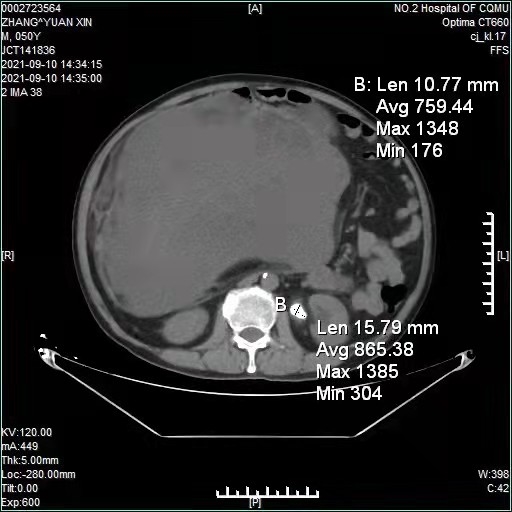

“本来是治疗肺结核,但却无意中查到了肚子里有个肿瘤。”来自九龙坡区的王先生因患有肺结核在外院进行治疗,但在8月17日进行胸+全腹部CT平扫检查时,医生却发现他的腹部有肿块,之后进行腹部增强CT检查,发现这个肿块非常大,几乎把整个腹腔盆腔都堵满了,考虑肿瘤性病变可能,在之后的穿刺活检,病理结果提示:恶性软组织瘤。

这一结果让王先生和家人非常震惊,因为除了肺结核之外,王先生身体没有任何其他异常症状,家人一直以为王先生只是啤酒肚而已,谁曾想里面居然是个恶性肿瘤。而且这颗肿瘤生长速度非常快,短短一个多月时间,又长大了很多。为了尽快进一步治疗,王先生于9月8日转入重医附二院,经过肿瘤中心进一步检查怀疑为恶性梭形细胞肿瘤。因为是实体性肿瘤,经过胃肠肛肠外科评估具备手术治疗的指征,王先生和家人非常希望能尽快切除这颗大肿瘤。

首先,这颗肿瘤简直是个“巨无霸”,霸占了整个腹腔,而且位置在腹膜后,压迫到了多支重要血管和脏器,患者的肿瘤并与多个脏器紧密粘连,包括肝脏、结肠、大网膜、广泛腹壁、肾脏、输尿管等,同时,肿瘤本身的血管网丰富,有多支腹腔动脉分支供应,手术切除过程中,极易引发无法控制的大出血,后果不堪设想。

得益于术前对病情的准确判断、准备充分,手术团队以往积累的丰富经验,以及麻醉科医生丰富的麻醉经验,整个手术及麻醉过程虽然惊险但很平稳,最终经过5个小时的抽丝剥茧,手术团度高质量完成了术前的最优手术方案,完整切除肿瘤10.67公斤,体积达7898立方厘米,且术中出血量不到100毫升。